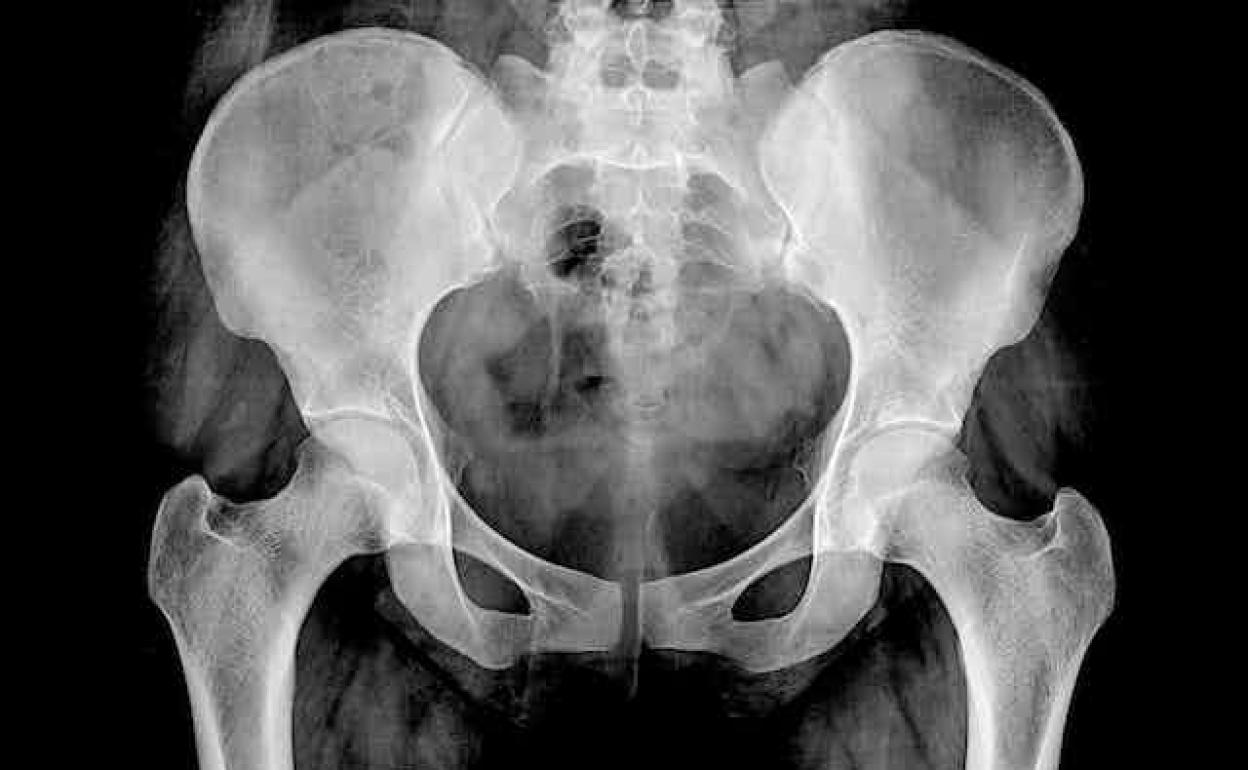

Vivir con el temor a fracturarse una vértebra, un brazo o la cadera. Es lo que sienten quienes padecen osteoporosis, que literalmente significa «hueso poroso». Consumir legumbres, lácteos, frutos secos y pescado azul puede aumentar la densidad de los huesos

Vivir con el temor a fracturarse una vértebra, un brazo o la cadera resulta fastidioso. Es lo que les pasa a quienes padecen osteoporosis, que literalmente significa «hueso poroso». La enfermedad se caracteriza por la reducción de la masa ósea y afecta al 30 % de las mujeres mayores de 50 años y al 8 % de los hombres.

La fragilidad ósea que acompaña a la osteoporosis reduce la calidad de vida de las personas que la padecen y se asocia con altas tasas de morbilidad y mortalidad. Además, en numerosas ocasiones se convierte en una enfermedad discapacitante.